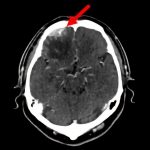

断層撮影

手術前1